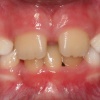

Diasteem – vahe esimeste hammaste vahel. Esineb 50%-l 6-8 aastastel lastel. Kuni 2 mm diasteemi puhul on, peale lateraalse intsisiivi ja silmahamba lõikumist, võimalik diasteemi iseeneslik sulgumine. Diasteem, mille suurus...